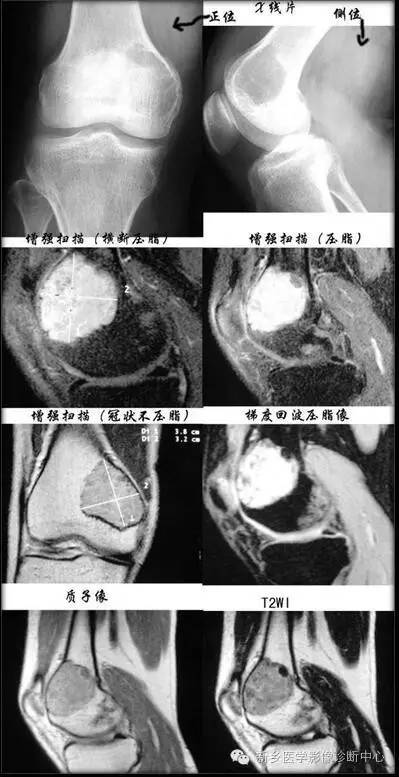

临床及影像特征:(关于骨良性纤维组织细胞瘤图片分析,见上图)1.年龄及病史:女性,32 岁,右膝关节疼痛一年2.病变的部位:右侧股骨内髁及干骺端3.病变的数目:单发,偏心性4.骨破坏的类型:地图样破坏,无明显膨胀性,其内未见骨嵴5.病变的边缘:边界清楚,可见硬化带6.病变基质的类型(肿瘤组织的成分):肿块内未见骨性及软骨性钙化。7.骨皮质改变:未见破坏。8.骨膜反应:未见明显骨膜反应9.软组织肿块:未见

本病主要应与以下两病鉴别:

① 骨巨细胞瘤:多呈膨胀性、偏心性骨质破坏,多房性骨破坏,骨皮质变薄,无骨硬化与骨膜反应,发生于膝关节周围,多累及骨端,血管造影多数有轻度至中度血运增加,均与良性纤维组织细胞瘤不同;组织学主要为纤维黄色组织,呈旋涡状,可见多核巨细胞及泡沫细胞,巨细胞较大且核数较多;而BFH梭形细胞和多核巨细胞体积较小,分布较稀疏,核数较少,泡沫细胞较多本组病例均发生于骨端,呈边界清楚的膨胀性溶骨性破坏术前误诊为骨巨细胞瘤,确诊须依靠病理。

②非骨化性纤维瘤:(1)发病年龄:非骨化性纤维瘤以10~20 岁以下青少年多见,BFH发病年龄更大些。(2)部位:非骨化性纤维瘤发生于长骨干骺端或骨干皮质,多数位于膝关节周围,呈偏心性、骨皮质稍膨胀变薄,但靠近髓腔侧硬化环均匀,不增厚,破坏区内有较多细小分隔,透过度较高;而骨BFH发病部位多见于长骨骨干、干骺端及骨骺、骨盆、肋骨,亦见于锁骨、颈椎椎体【良性纤维组织细胞瘤好发于髂骨和肋骨(该处从不发生非骨化性纤维瘤),也可见于长骨干,多位于骨干中央,偶见于骨骺端】。(3)临床:非骨化性纤维瘤常为多发,临床症状不明显,无疼痛,发生病理骨折后出现疼痛,有自愈倾向;而BFH疼痛明显,手术刮除后有复发倾向。(4)组织学:二者组织学表现相似,但BFH泡沫细胞相对多些。干骺端纤维性缺损发生于小儿,且成年能自愈,无临床症状,发生于干骺端皮质内,病变范围小,属瘤样病变;若病变范围较大,累及髓腔并形成肿块,即为非骨化性纤维瘤。

③骨恶性纤维组织细胞瘤:多呈溶骨性骨质破坏,偏心性生长,边界不清,无残留骨嵴和硬化边,皮质常中断缺损,侵犯周围软组织;细胞有明显的多形性、异型性和病理性核分裂像,容易鉴别。骨良性纤维组织细胞瘤预后不佳,切除后容易复发,极少数不典型病例发生肺转移。正确诊断此病,有助于临床治疗,扩大切除范围,根治此病。